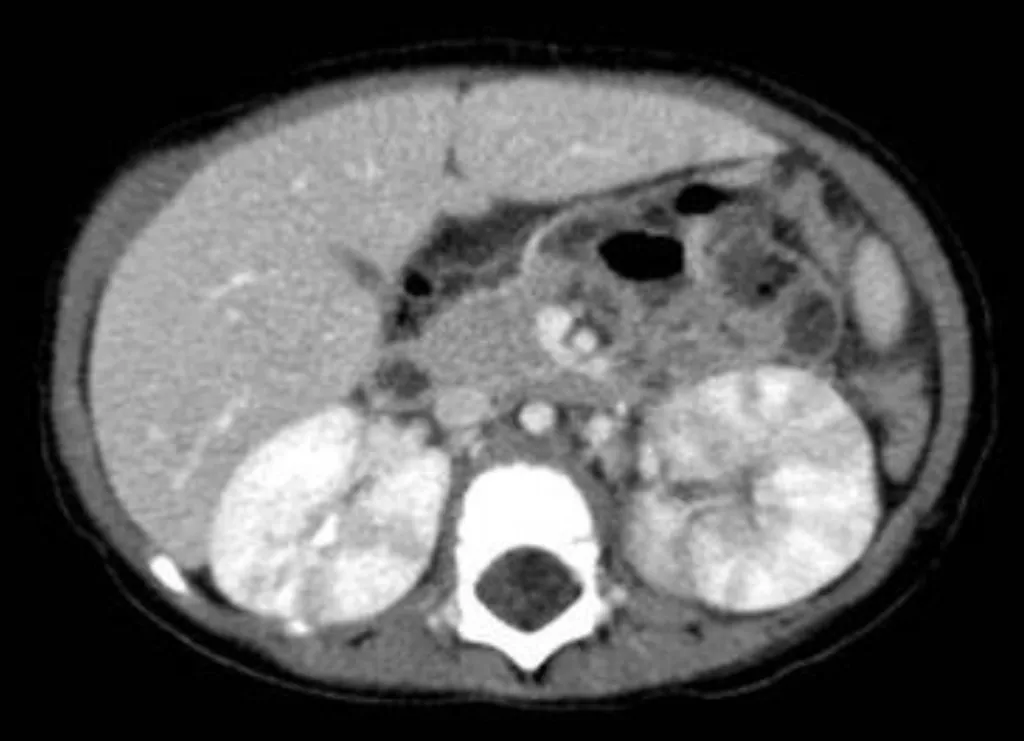

【114-1 醫學(四) 第14題】

5 歲女童高燒 3 日及膿尿(pyuria ; WBC 100~150/HPF),住院接受抗生素治療。經投與經驗性抗生素治療 3 日後,高燒並沒有改善。腹部電腦斷層(有注射顯影劑)檢查顯示如圖,女童最可能的診斷為:

詳解

破題關鍵

這張腹部電腦斷層影像顯示腎臟有不均勻的顯影,特別是右腎出現多處條紋狀或楔形低密度病灶,這是急性大葉性腎盂腎炎的典型表現。

選項拆解